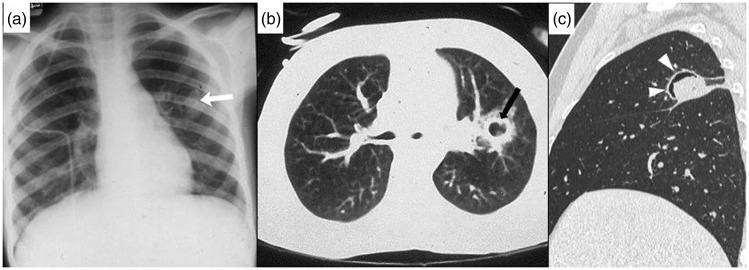

The purpose of this current pictorial review is to define the solitary round pulmonary lesion (SRPL), to familiarize with its prevalence in the pediatric population, and, moreover, to educate radiologists on its vast differential diagnosis and imaging manifestations. Furthermore, by highlighting valuable clues, it intends to assist radiologists efficiently partake in its diagnosis, work-up, and follow-up in order to narrow down the differential diagnosis by working alongside the clinician and combining clinical information, lab results, and radiological findings.

本次影像综述的目的是明确孤立性圆形肺病变(SRPL),使其在儿科人群中的患病率,此外,使放射科医生熟悉其广泛的鉴别诊断和影像学表现。此外,通过强调有价值的线索,旨在帮助放射科医生有效地参与其诊断、检查和随访,以便通过与临床医生合作并结合临床信息、实验室结果和影像学发现来缩小鉴别诊断范围。